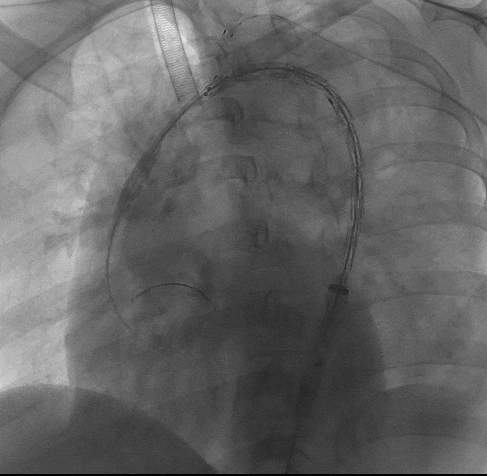

3、再次造影确认支架位置准确后,快速释放主体支架,助手配合牵拉分支导丝释放分支支架。

动脉长鞘怎么置入宁波市第二医院血管外科运用Castor®单分支支架结合长鞘建立导丝通路的方法治疗Stanford B型胸主动脉夹层一例_https://www.jmylbn.com_新闻资讯_第10张

释放主体支架

动脉长鞘怎么置入宁波市第二医院血管外科运用Castor®单分支支架结合长鞘建立导丝通路的方法治疗Stanford B型胸主动脉夹层一例_https://www.jmylbn.com_新闻资讯_第11张

牵拉分支导丝释放分支

4、术后造影显示,主动脉夹层第一破口被有效隔绝,LSA血流通畅,真腔得到有效重塑,支架无移位或内漏现象发生,手术圆满成功。

动脉长鞘怎么置入宁波市第二医院血管外科运用Castor®单分支支架结合长鞘建立导丝通路的方法治疗Stanford B型胸主动脉夹层一例_https://www.jmylbn.com_新闻资讯_第12张

术后造影

动脉长鞘怎么置入宁波市第二医院血管外科运用Castor®单分支支架结合长鞘建立导丝通路的方法治疗Stanford B型胸主动脉夹层一例_https://www.jmylbn.com_新闻资讯_第13张

术后造影(胸腹主动脉)